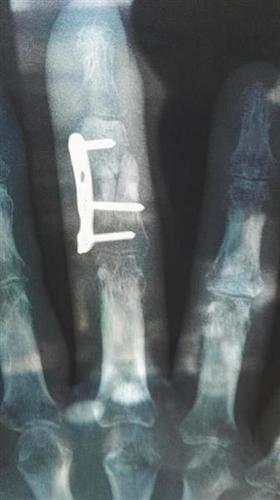

杨先生3月5日所照的X光片显示伤处仍未愈合。